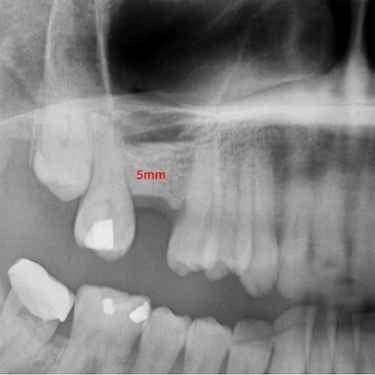

Durante esta valoración inicial, realizamos un escáner 3D o TAC dental de alta precisión que nos permite observar en detalle la cantidad y calidad del hueso disponible.

Esta imagen tridimensional nos ayuda a planificar el injerto con total seguridad, definiendo el volumen necesario y localizando estructuras anatómicas importantes como el nervio dentario o el seno maxilar.

Todo comienza con una primera consulta en la que realizamos pruebas y analizamos la zona para ver la cantidad de injerto que se va a necesitar y determinamos con el paciente cómo será el proceso que seguiremos.